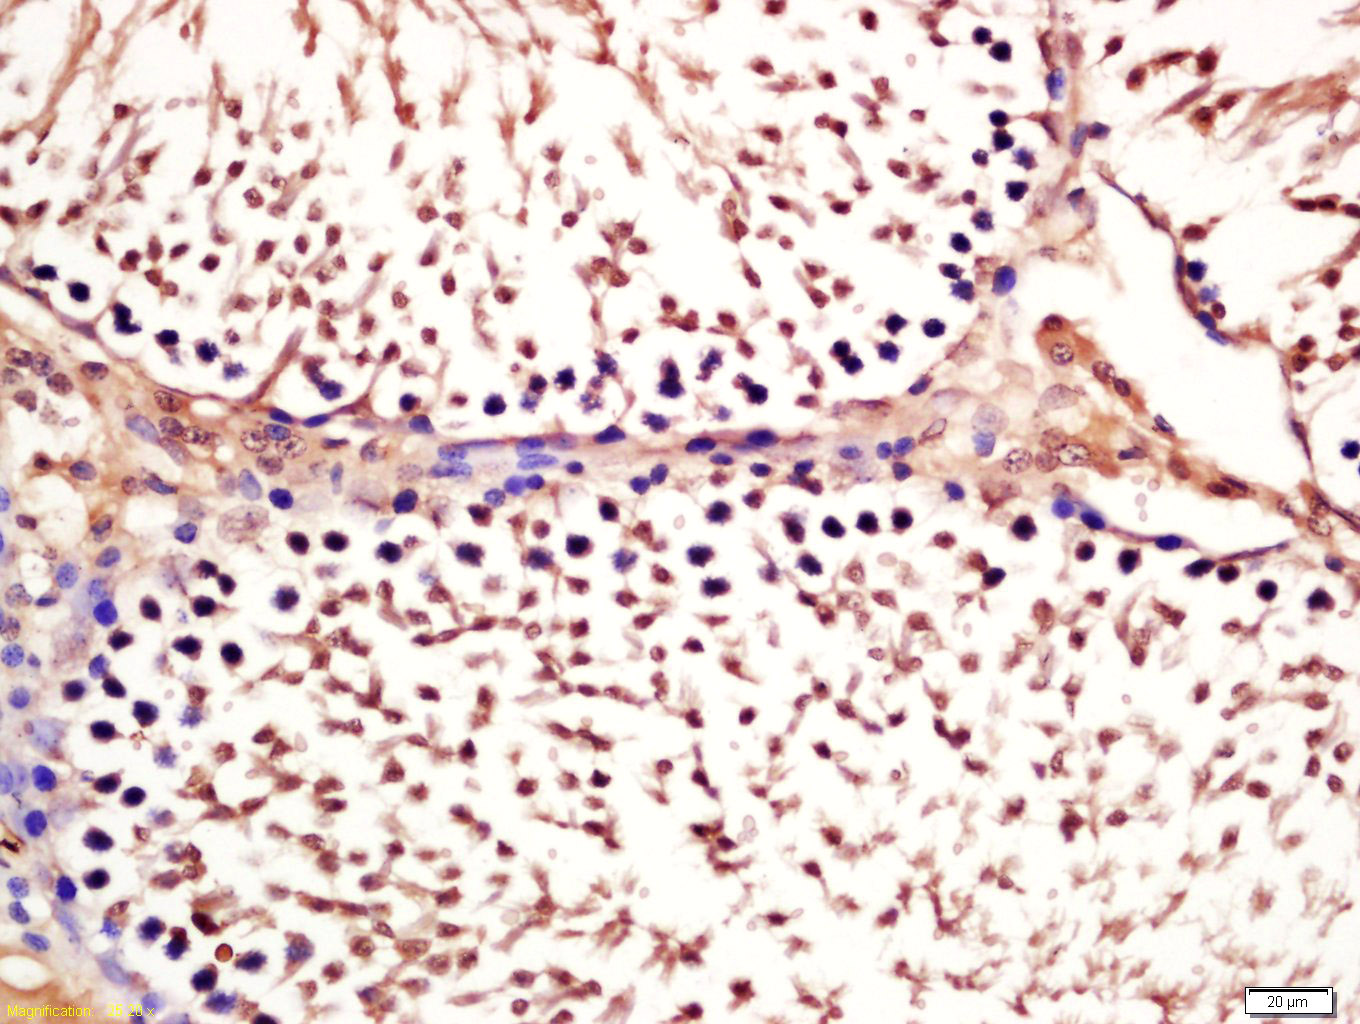

Tissue/cell: rat testis tissue; 4% Paraformaldehyde-fixed and paraffin-embedded; Antigen retrieval: citrate buffer ( 0.01M, pH 6.0 ), Boiling bathing for 15min; Block endogenous peroxidase by 3% Hydrogen peroxide for 30min; Blocking buffer (normal goat serum,C-0005) at 37℃ for 20 min; Incubation: Anti-phospho-GSK-3 Beta (Ser21) Polyclonal Antibody, Unconjugated(bs-5368R) 1:200, overnight at 4°C, followed by conjugation to the secondary antibody(SP-0023) and DAB(C-0010) staining